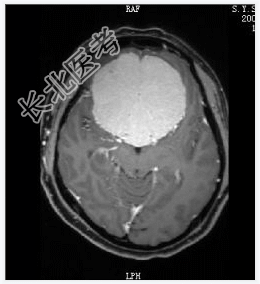

- [材料题] 患者女,55岁,视力下降数月。查体:视力下降,余神经体征阴性。

- 简答题1、诊断及依据是什么?

- 简答题2、鉴别诊断有什么?